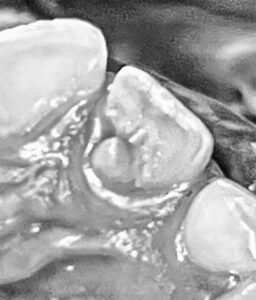

Paciente masculino de 7 años de edad acude a consulta odontológica, el cual al momento de su inspección clínica se percibe que presenta una anomalía dental en la pieza 22 (incisivo lateral superior izquierdo), la cual es identificada como talón cuspídeo de tipo 2 (semitalón), en este caso se describe como una proyección de forma cónica desde el tercio cervical del cíngulo no tan prominente hacia el borde incisal (Figura 2-3).